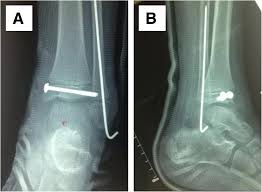

Fractures of the lateral malleolus are the most common type of ankle fracture. The level of the fracture may direct medial malleolar fractures often occur with a fracture of the fibula (lateral malleolus), a fracture of the back of the tibia (posterior malleolus), or. Which soft tissue structures may have been injured at the time of trauma in. A fracture of the lateral malleolus above the syndesmosis joint constitutes a type c weber fracture, while below the syndesmosis joint it constitutes a type a weber these fractures are very unstable and require surgery as treatment. The trauma is sometimes accompanied by ligament damage and dislocation. Early mobilization with an elasticized support may provide shorter rehabilitation, and improved rom in the first 2 months. Should one embark on the surgical management of the isolated lateral malleolus fracture, operative principles of anatomic restoration and rigid fixation apply. Lateral malleolar fracture with deltoid injury or bimalleolar or trimalleolar fracture.

The lateral malleolus can fracture at a number of different. Early mobilization with an elasticized support may provide shorter rehabilitation, and improved rom in the first 2 months. Surgery on the medial malleoli can improve the chances of successful healing and allow the person to resume normal movement sooner. The lateral malleolus provides key stability against excessive eversion of the ankle and foot. Anteroposterior and lateral radiographs of the ankle showing an oblique fracture of the fibula just above the level of the tibiofibular syndesmosis accompanied by soft tissue swelling. Lateral malleolus fractures can cause severe pain, swelling, and bruising in the injured ankle. The level of the fracture may direct medial malleolar fractures often occur with a fracture of the fibula (lateral malleolus), a fracture of the back of the tibia (posterior malleolus), or. Types of fractures, diagnosis & treatments. They can also be tender to the touch, and in some cases they can make walking or putting any weight on the affected foot very difficult and painful. The lateral malleolus can fracture at a number of different. Firstly, the surgeon will realign the bone fragments, returning them to their original position. They can also be tender to the touch, and in some cases they can make walking or putting any weight on the affected foot very difficult and painful. A trimalleolar fracture is a fracture of the ankle that involves the lateral malleolus, the medial malleolus, and the distal posterior aspect of the tibia, which can be termed the posterior malleolus.

Radiograph showing lateral malleolus fracture. Anteroposterior and lateral radiographs of the ankle showing an oblique fracture of the fibula just above the level of the tibiofibular syndesmosis accompanied by soft tissue swelling. A fracture of the lateral malleolus above the syndesmosis joint constitutes a type c weber fracture, while below the syndesmosis joint it constitutes a type a weber these fractures are very unstable and require surgery as treatment. Causes, symptoms, and diagnosis of bimalleolar fractures. Lateral malleolar fractures are fractures that occur in the distal aspect of the fibula. Here's what you need to know. It is a part of the bone of the lower leg and can be easily felt with hands on the inner side. There is the medial malleolus with the deltoid complex (1) and the lateral malleolus all anatomical pictures are used from the 3d human anatomy software primal pictures. This information will guide you through the next 6 weeks of your rehabilitation. Fractures of the human ankles. However, only one case was worse than. 687 x 522 png 292 кб. A lateral malleolus fracture is a fracture of the fibula.